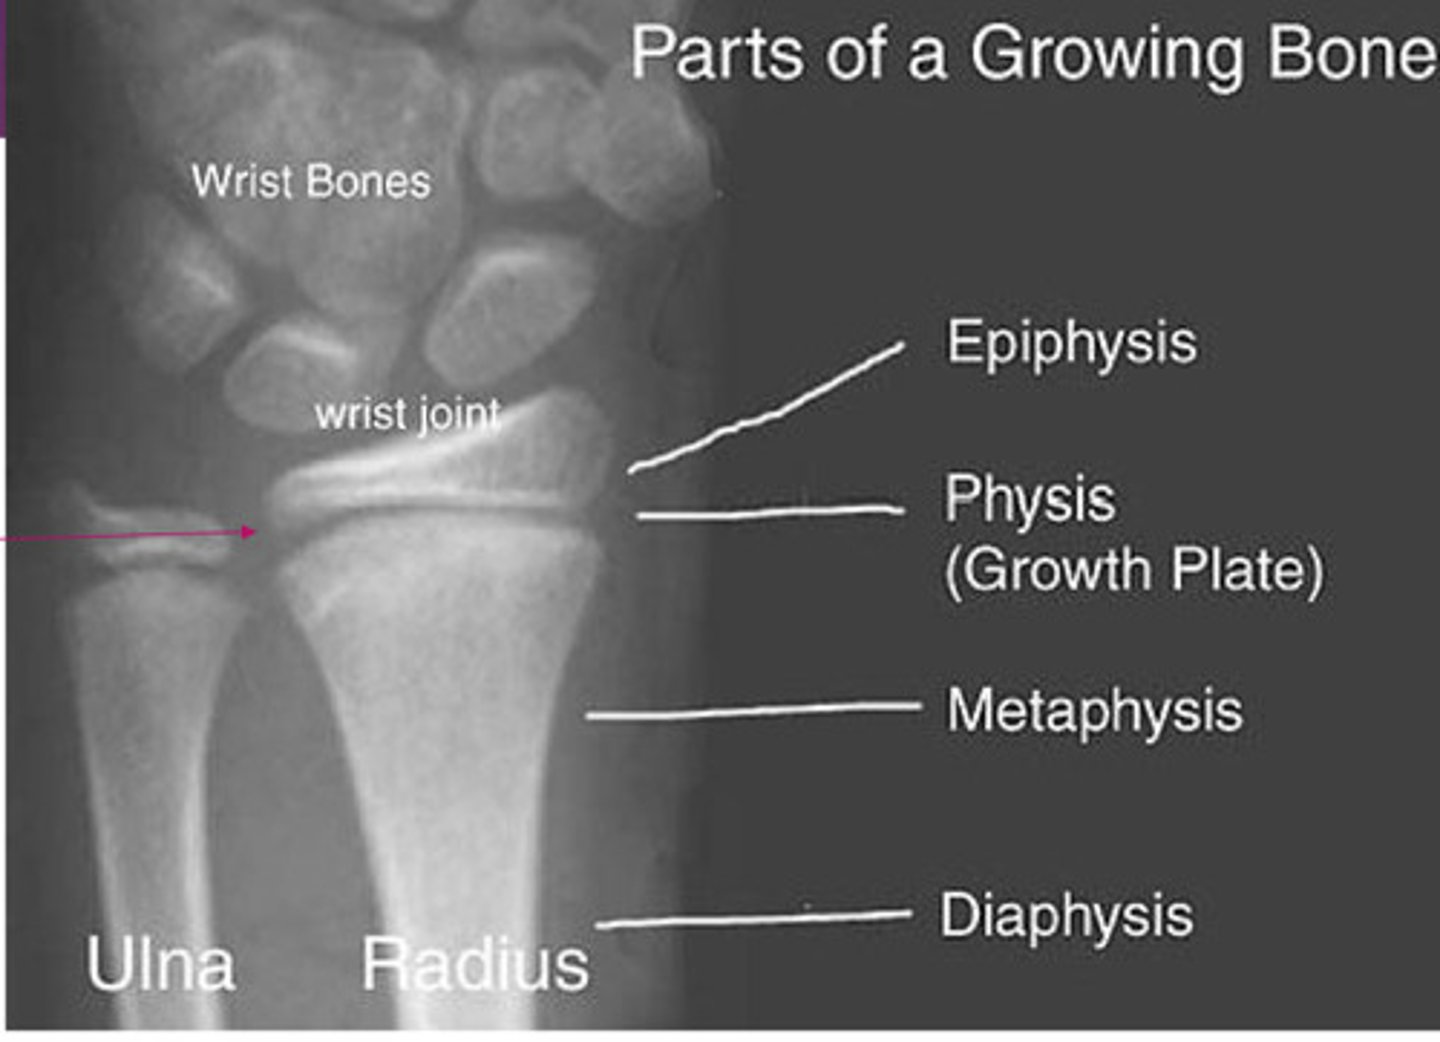

normal xray of growing bone

type 1 salter harris fracture

through the growth plate; heals well w/ cast

type II salter harris fracture

through the growth plate & metaphysis; heals well w/ cast

type III salter harris fracture

through growth plate & epiphysis; can develop arthritic changes or asymmetrical growth plate fusion

type IV salter harris fracture

through all 3 elements: growth plate, metaphysis and epiphysis; more likely to develop early fusion of growth plate w/ angular deformities & shortening of bone

type V salter harris fracture

crush injury to growth plate; more likely to develop early fusion of growth plate w/ angular deformities & shortening of bone; associated w/ vascular injury & cause growth impairment